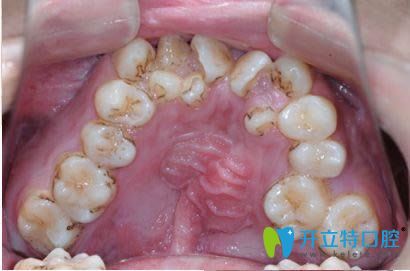

牙齒矯正是采用佩戴可摘矯治器或固定矯正器附于牙齒上,通過(guò)相應(yīng)的加力使牙齒從原本的位置,移動(dòng)到設(shè)計(jì)好的位置,以此來(lái)達(dá)到整平牙列,關(guān)閉間隙,穩(wěn)定咬合關(guān)系的目的。

我們的牙齒是通過(guò)牙周膜與牙槽骨相連并保持獨(dú)立的,本身在行使正常口腔功能時(shí)就可以在一定程度內(nèi)進(jìn)行改建和重塑。而矯正這個(gè)移動(dòng)的過(guò)程是緩慢的,用力輕微,是不會(huì)傷害牙齒和牙槽骨的,當(dāng)矯治結(jié)束后牙齒在牙槽窩完成重建,牙齒就會(huì)穩(wěn)固。

因此,正規(guī)合理的牙齒矯正是不會(huì)導(dǎo)致牙齒松動(dòng)脫落,反而當(dāng)牙列排齊后,便于牙齒的清潔,而會(huì)利于牙周健康,使牙齒更穩(wěn)固。

張?jiān)洪L(zhǎng)表示,首先,年齡大了以后,牙齒是否會(huì)早掉,主要取決于牙周情況的好壞(包括牙周膜、牙槽骨、牙齦),還有就是蛀牙齲齒的因素。整個(gè)牙齒被蛀空了容易掉,當(dāng)牙周長(zhǎng)期炎癥侵蝕,導(dǎo)致骨頭吸收,就如水土流失一般,牙齒也容易掉。而引起牙周炎的往往是牙齒菌斑微生物和牙結(jié)石。

牙齒不齊容易引起牙周病及齲齒

因此,從長(zhǎng)期來(lái)看,老了容易掉牙的元兇是牙周疾病和嚴(yán)重齲壞。但是還要提醒的一點(diǎn)是,在剛剛?cè)コ捞讜r(shí),牙齒是有一定程度的活動(dòng)度。因?yàn)榇藭r(shí)牙齒位置尚不穩(wěn)定,很容易向矯正前的方向反彈,因此需要佩戴保持器,在經(jīng)過(guò)一段時(shí)間之后,牙齒就會(huì)達(dá)到正常穩(wěn)固水平。